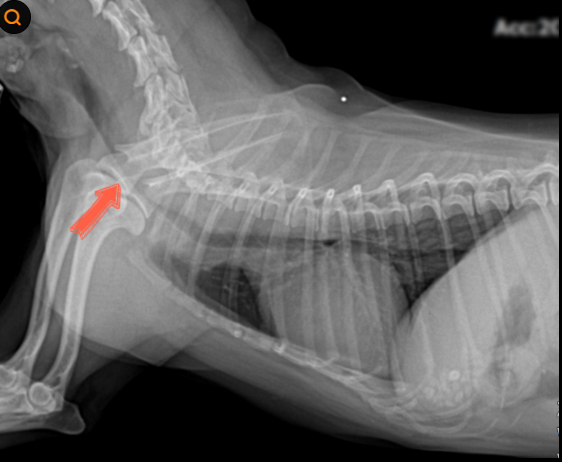

| X-ray | 5~10만원 |

포메라니안 6세가 헐떡임과 기침을 보였습니다. 원인은 목줄 사용으로 인한 기관 압박이었습니다.

Q2 기관허탈은 완치가 가능한가요?

| 강아지 기관허탈 초기증상 체크리스트 (1) | 2026.03.03 |